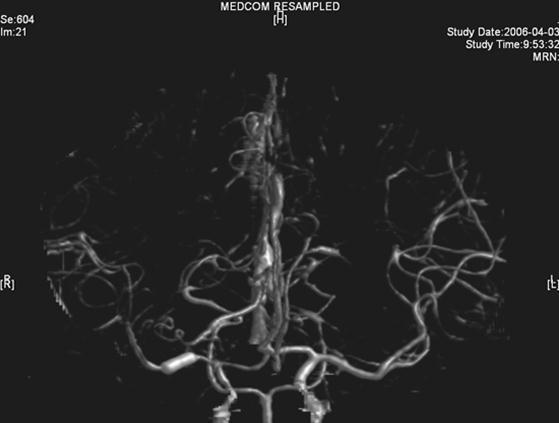

A twenty-nine-year-old female was admitted in Feb, 2006 because of episodic left limb numbness and weakness for half a year. The duration of the episode lasted for a few minutes, seldom over ten minutes. There was an attack every several days. She denied special medical history. She did not live in the pandemic area of Leptospirosis. Her blood pressure was 110/65mmHg and body weight was 51 kilograms. Physical examination found no abnormality. Magnetic resonance angiogram (MRA) (Feb 22) showed severe stenosis in the M1 segment of right MCA. In the source images of MRA, an oval area of abnormal signal in the right basal ganglion was found (Figure 1). Blood routines, coagulation tests, blood biochemistry tests, and C-reactive protein level were normal. The anti-nuclear antibody (ANA), anti-extractable nuclear antigen (ENA) antibodies, and anti-neutrophil cytoplasmic antibodies (ANCA) were negative. Serologic test for Syphilis was negative. Blood sedimentation rate (ESR) was 20 mm/h, and the level of anti-streptolysin O microtitration test (ASO) was 395 IU/ml (0-200 IU/ml). Digital subtraction angiography (DSA) detected severe stenosis (95%) in M1 segment of the right MCA, and the distal blood flow was compromised (Figure 2). The patient was given aspirin 100mg/d, clopidogrel 75mg/d and atorvastatin 20mg/d since Feb 26. Due to the finding of high ASO level, she was given penicillin (4 million IU, bid) for a week. Because of disagreement between the consulting physician and the interventional radiologist, her angioplasty and stenting was delayed till Mar 21 on her request. During the waiting time, her attacks did not reduce. Before the operation, besides the combination of aspirin and clopidogrel, subcutaneous low molecular weight heparin (LMWH) (5000U, q12h) was given for 5 days. After a complete diagnostic evaluation of the blood vessels with DSA, stenting was performed with a stainless steel stent 2.75 mm in diameter by 1.5 cm in length (PC, Abott Company) at the presure of 7 atm. No compromise of perforating branches was found and residual stenosis was less than ten percent on angiography (Figure 2).

Figure 2.Right MCA before and after angioplasty and stenting

Right MCA before and after angioplasty and stenting

Figure 4.CTA image

CTA image

The right MCA stenosis, which led to the transient ischemic attack (TIA) symptoms, was definitely diagnosed. Angioplasty and stenting was conducted after full preparation of dual anti-platelet therapy. Immediately before the operation, LMWH was used in combination and was continued after operation. Her condition was stable in the first two days after operation. Then crescendo TIA recurred and led to motor impairment. Two lesions were shown in the emergent CT images. One was near the anterior horn of the right lateral ventricle, by which it was difficult to explain the symptoms and physical signs. The other was in basal ganglia, and was related to the symptoms and signs. The signal in this region had been slightly higher than the counterpart in the left in the source image of MRA before operation. Hence the lesion in basal ganglia was thought to result from hemodynamic impairment in distal parts of stenotic MCA. Both lesions had clear boundaries, which indicated that the infarction in the area supplied by deep branch of MCA occurred before the TIA attacks. The crescendo TIA worsened gradually, but got partial recovery after volume expansion treatment initially. TCD test showed the blood flow velocity increased in both ACA, especially in the right, while that in the right MCA did not significantly increase. This indicated that some collateral circulation had formed, to counteract hypoperfusion caused by progressive stenosis in the right MCA. Based on these, we deduced that there was IST which did not completely block the right MCA. The symptoms and physical signs appeared again when there was failure of collateral compensation. Because there were new lesions on CT scan and the patient had been treated with dual anti-platelet treatment and anticoagulation, thrombolytic therapy could not be given. So we gave unfractionated heparin (UFH). The symptoms and physical signs disappeared on the next day. But two days later during the same treatment, the symptoms and signs recurred, volume expansion was ineffective, this indicated that initial recovery of symptoms was due to compensatory collateral circulation, and anticoagulation therapy with UFH may also play a role. But this could not prevent thrombosis from progressing, so we increased the dose of anticoagulation drugs, the symptoms and signs disappeared eventually. CTA (Apr 3) and repeated TCD (Apr 17) confirmed our reasoning with attenuated proximal lumen of right MCA and increased blood flow velocities of the right MCA and ICA.